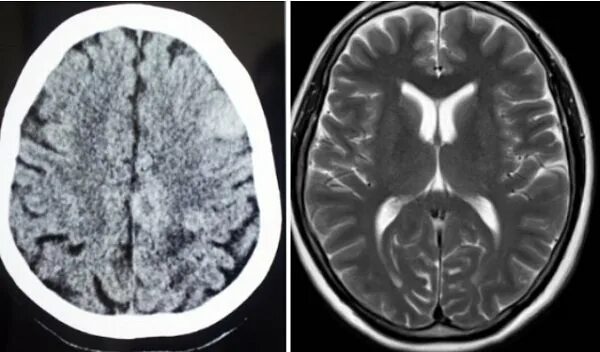

Рентген и мрт в чем разница